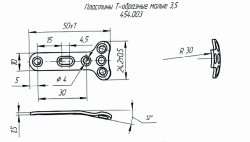

Small T-Shaped Plates 3.5, Article 454.003

US$9-36

Material:

Titanium alloy

Material:

Titanium alloy

OSTEOMED-M LLC 🇷🇺